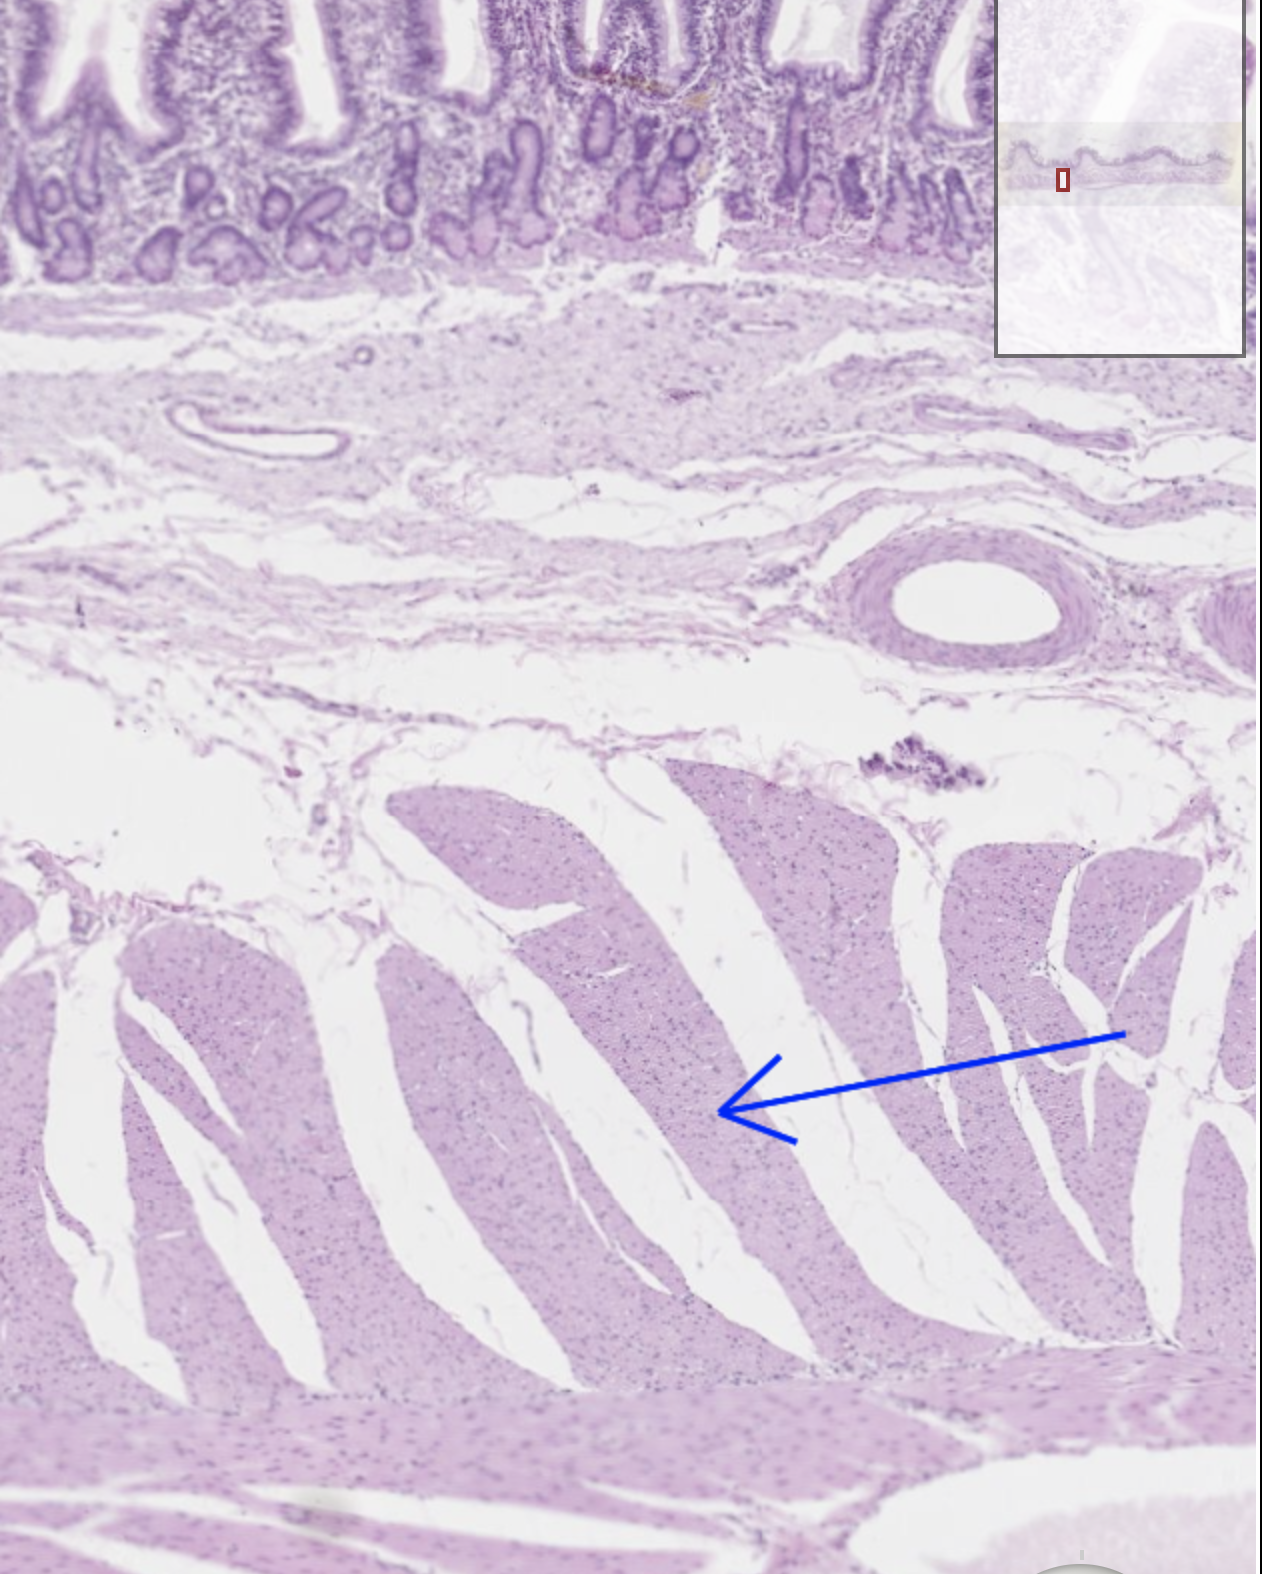

13

Q

Je kijkt naar een skeletspier van een veulen. Wat wordt er hier aangewezen?

A

Het perimysium

Geef in dit plaatje het perimysium, endomysium, een spiercel, en een nucleus van een spiercel aan

Rode pijl = perimysium

Gele pijl = endomysium

Zwarte pijl = nucleus van een spiercel

Gele cirkel = spiercel

Rode cirkel = doorsnede van myofibrillen